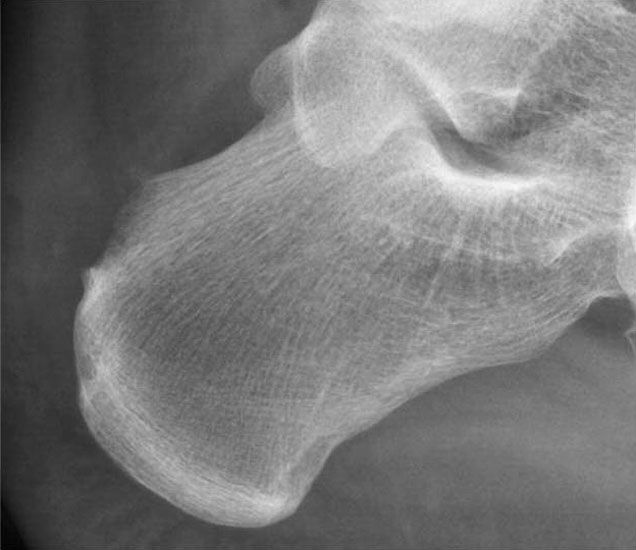

• Seitliches Röntgenbild der Ferse.

Abbildung 11-12

Prä- und postoperatives Röntgenbild.